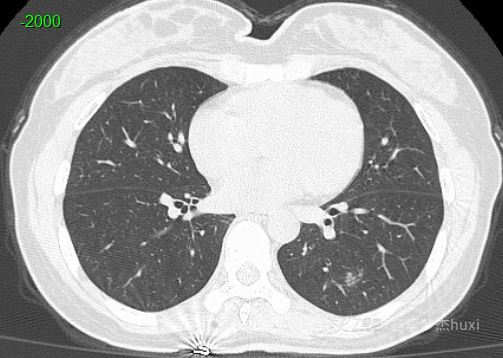

病例女性45岁,体检发现PET-CT阴性的肺结节,猜病理。

患者性别:女

患者年龄:45岁

主诉:体检发现肺结节,PET-CT阴性。